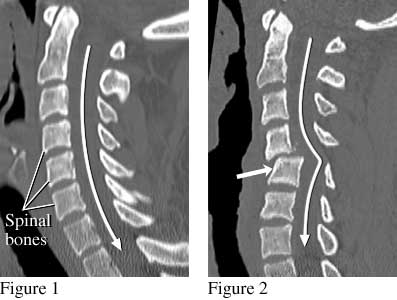

Cervical Spine (Neck) CT Scan